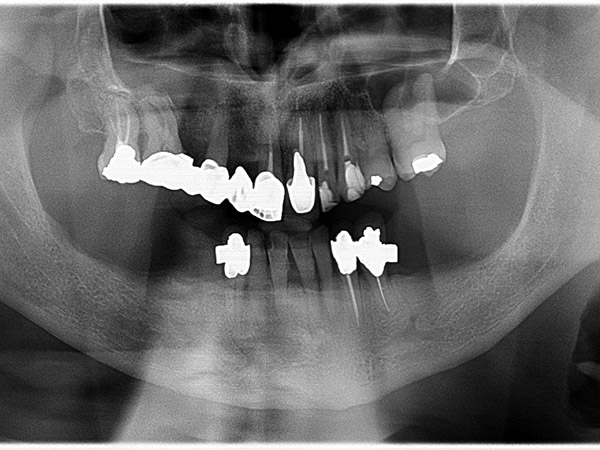

Impianti AZ Implant DX in riabilitazione completa inferiore fissa avvitata con grave terza classe scheletrica

Impianti dentali in riabilitazione inferiore per supportare struttura fissa avvitata con grave terza classe scheletrica.

L’intervento nello specifico è stato realizzato dal Dr. Andrea Tomasinelli con componenti protesiche progettate e fornite da AZ Implant.